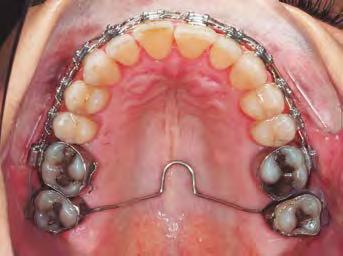

–MARPE, una alternativa a la disyunción en el paciente adulto, por el Dr. Enrique Solano y cols. [88]